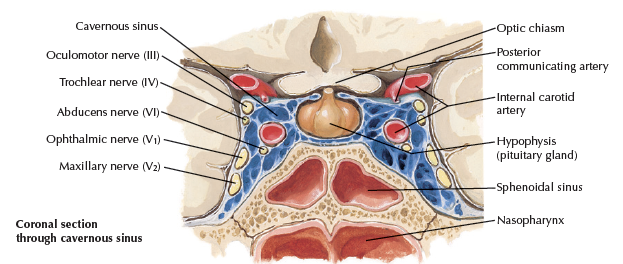

Internal carotid a.

- 進入carotid canal 前無分支

- CN X 伴行

- Carotid canal入顱

Sphenoid bone

Foramen rotundum

Foramen ovale

Foramen spinosum

Pterygoid canal

Foramen lacerum (破裂孔)

Optic canal

- CN II

- Ophthalmic a.

Sup. orbital fissure

- Ophthalmic n.(CN V1)/ v.

- CN III, IV, VI

Hypophyseal fossa

腦下垂體在這